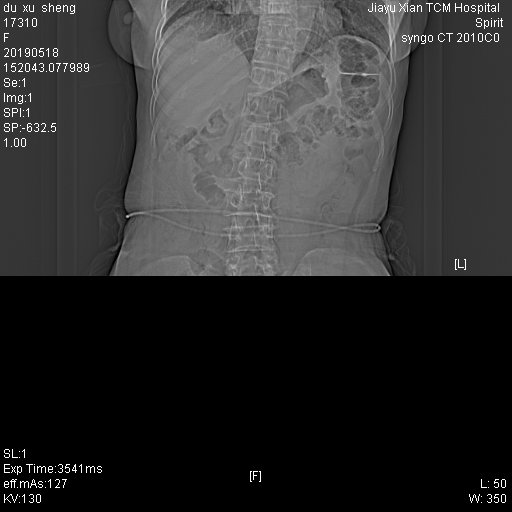

CT53625:腹部

患者性别:女 患者年龄:70 简要病史:右下腹疼痛,5天未解大便 辅助检查:白细胞12

右下腹相当盲肠周围脂肪间隙密度稍增高且较模糊。右侧胸膜轻度增厚。提示:盲肠周围炎可能。

阑尾炎并周围脓肿形成。两侧胸腔小量积液。

阑尾炎并周围脓肿形成。